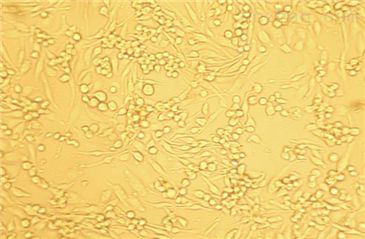

RKO(结肠腺癌细胞)全程提供细胞生物体、生长特性、来源、器官、类型、形态、培养条件、应用、组织、冻存条件等复苏及冻存细胞株说明书信息,专业的技术支持您的细胞系实验,让您实验再无烦扰!培养的前一周内出现质量问题,客户可凭细胞的照片以及书面形式的细胞培养,实验操作过程提供给我司。经技术人员核实认定为可以予以重发的情况,由我司再免费提供一次细胞。